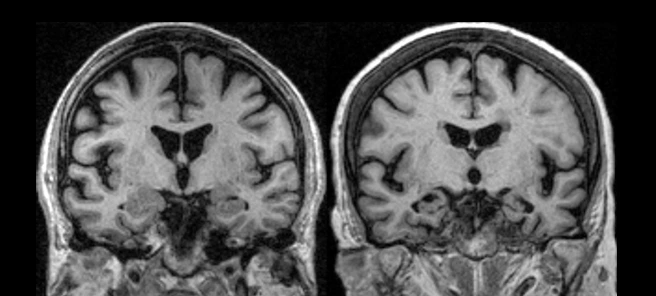

아버지의 뇌 MRI 사진을 보았다.

쪼그라든 호두 같았다.

나비의 실루엣 같기도 했고

까마득한 기억 너머 미술 시간에 그려봤던

데칼코마니 그림 숙제 같기도 했다.

전두엽 사진인데요

사이사이 빈 공간 보이시죠?

원래 저런 곳이 꽉 차 있어야 좋은 건데

아버님 뇌는 많이 쪼그라든 상태예요

연세와 교육 수준의 평균치에 비해

뇌 상태 수치가 많이 낮아요

그러다 보니 전두엽이 관장하는

기억력, 인지 능력, 사고 능력 등이

많이 떨어져 있는 상태고요

감정 조절도 안 돼서 갑자기 화를 내거나

신경질을 내거나 폭력적이 되기도 할 거예요

망상, 집착, 의심 등이 주요 증상이고요

건강한 사람들은 의식의 거름망이란 게 있거든요

보통의 이성적인 사람들은

화가 나거나 욕을 하고 싶거나 상상을 해도

그걸 순화하거나 아예 입 밖에 내질 않잖아요

그런데 아버님은 지금 그 거름망이 없는 상태예요

그래서 하고 싶은 대로 하는 거예요

가족을 일부러 괴롭히려는 게 아니고

자기도 제어나 통제가 안 되는 상태인 거예요

성격도 바뀌어서 지금 보고 계신 아버지는

가족들이 일던 그 사람이 아닌 거예요

그러니 가족들이 이해해 주셔야 해요

젊디젊은 의사선생님이 MRI 사진을 보며

해주던 말들이 아득한 메아리처럼 흩어졌다.